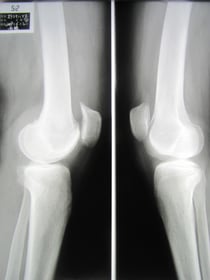

○変形性膝関節症

年齢を重ねると関節の軟骨も徐々に摩耗していきます。日常の負担、体重、運動不足など

も大きな要因です。

整形外科では注射によりヒアルロン酸の注入により負担を軽減させますが、私たちは理学療法により

関節の柔軟性と血行促進 筋力強化運動をします。